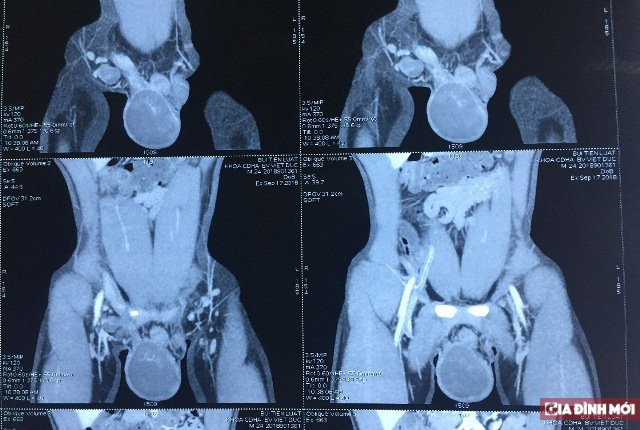

Kết quả thăm khám lâm sàng thấy bệnh nhân có tinh hoàn phải to chắc ấn đau, biến đổi hình thái, tinh hoàn trái nhỏ. Hình ảnh chụp CT chỉ rõ hình ảnh u tinh hoàn phải không xâm lấn ra vỏ tinh hoàn và các tổ chức lân cận.

U tinh hoàn của bệnh nhân.